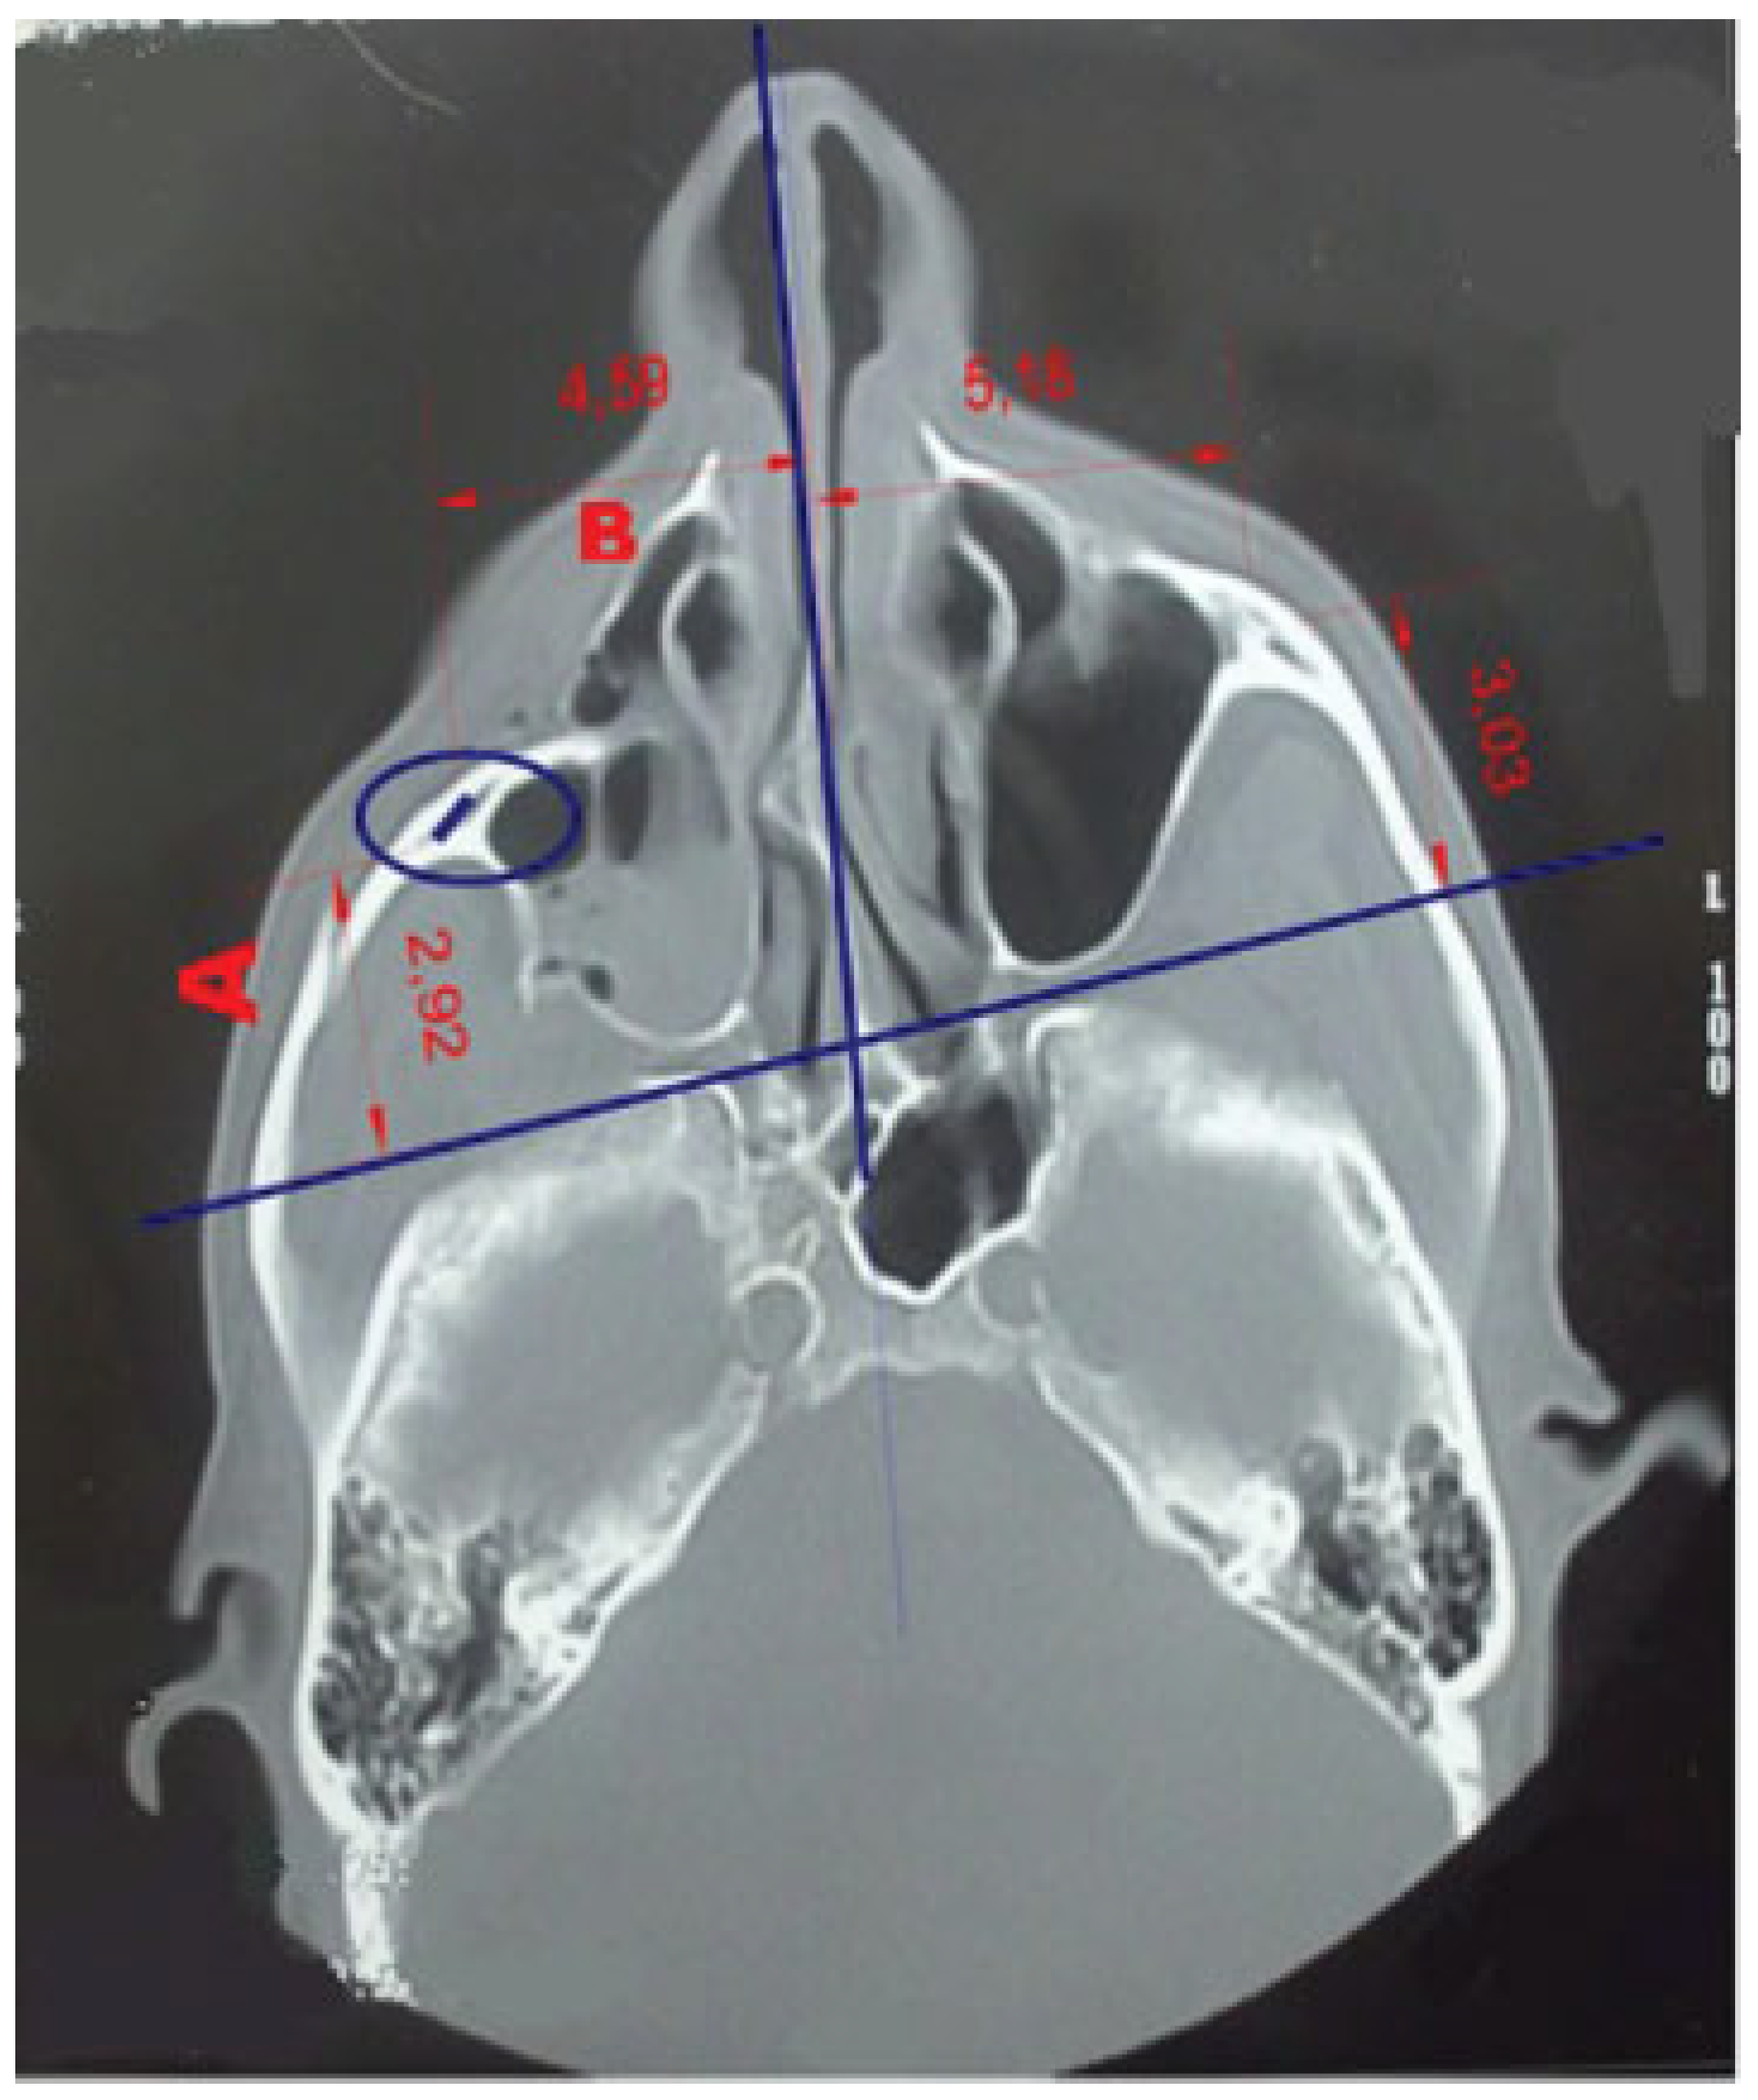

• Zygomatic width (corresponding to x-axis): Compare the lateral presentation of zygoma on both sides at the level of OMC by measuring the distance between the reference line (nasal septum) and center of zygoma (distance B; measurements in cm).

• Zygomatic height (corresponding to y-axis): Compare the distance between the horizontal reference line (at the roof of the bony orbit) and the point at the center of zygoma on both sides at the level of OMC (distance C; measurements in cm; Figure 2).[5]

Figure 2. Radiological assessment of zygomatic position in coronal view at the level of OMC. Distance B—Zygomatic width: lateral presentation of zygoma from nasal septum (reference line) and center of zygoma (measurements in cm). Distance C—Zygomatic height: superoinferior distance forms roof of the bony orbit (reference line) and center of zygoma (measurements in cm).